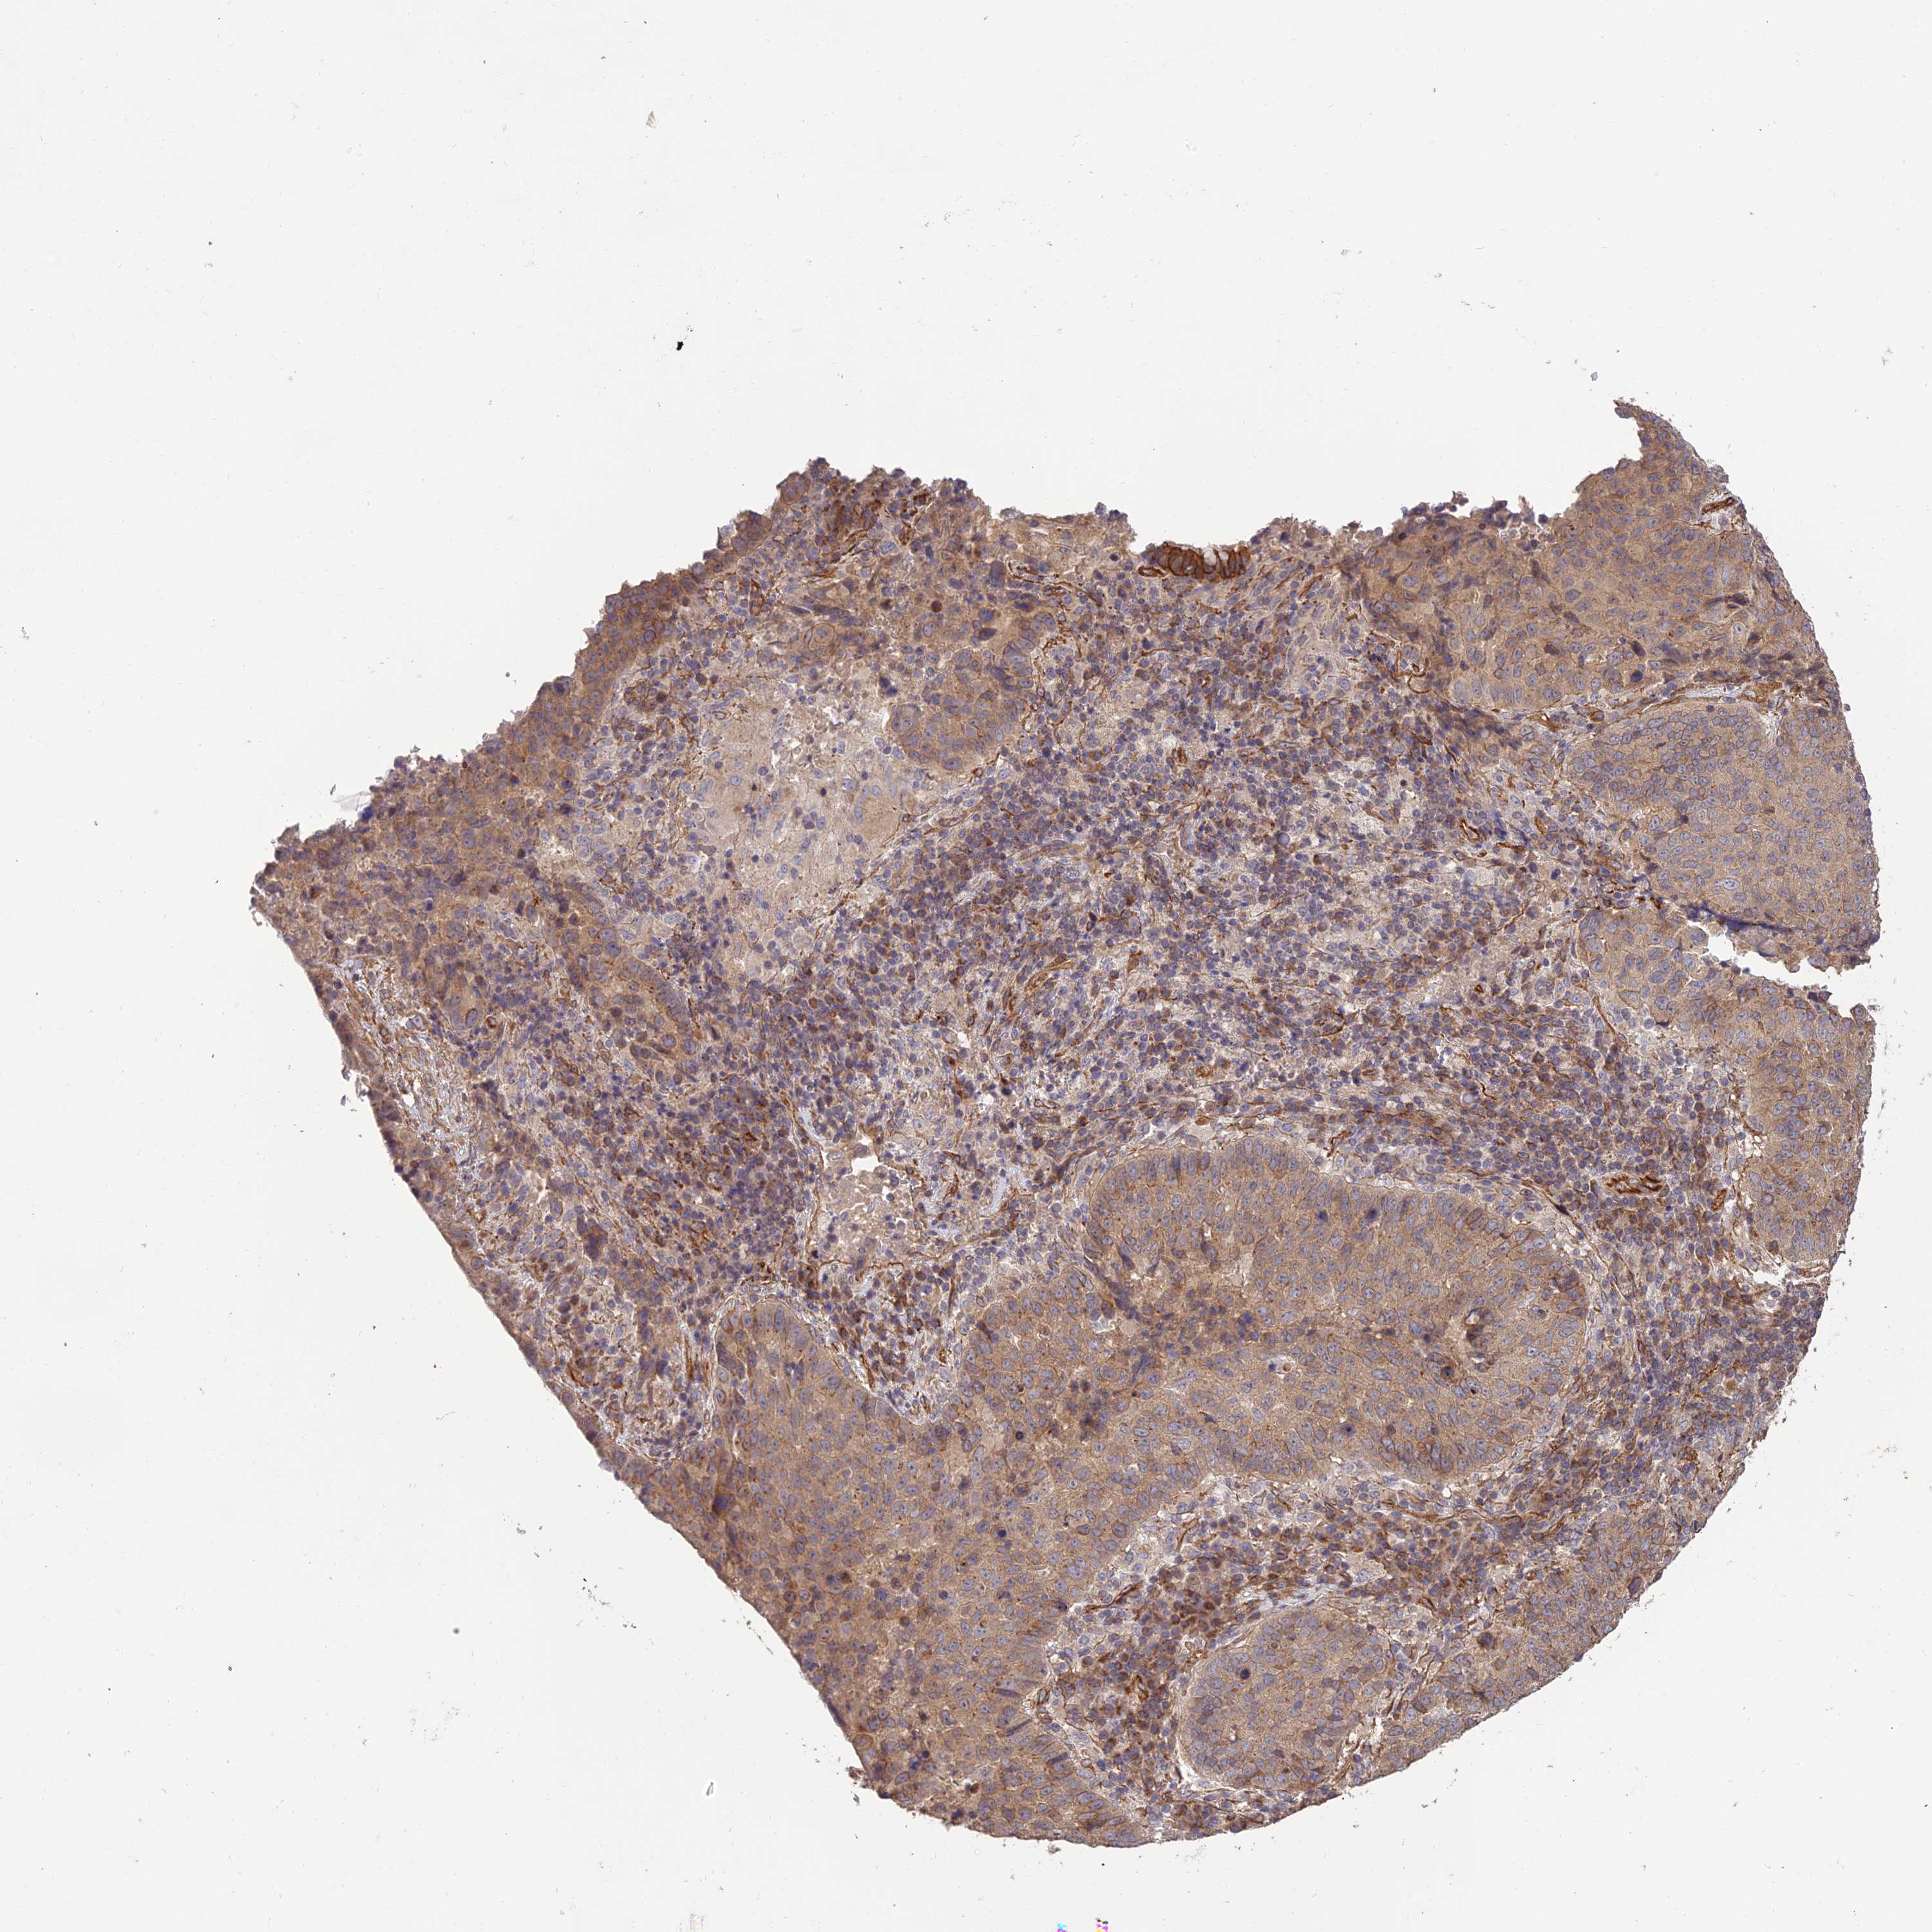

CANCER LUNG CANCER Show tissue menu

LUAD TCGA LUAD VALIDATION LUSC TCGA LUSC VALIDATION PROTEIN LUAD CPTAC PROTEIN LUSC CPTAC PROTEIN EXPRESSION

HOMER2 is not prognostic in Lung Adenocarcinoma (validation)

HOMER2 is not prognostic in Lung Squamous Cell Carcinoma (TCGA)